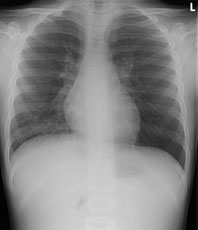

Radiologie Quiz 45

Zur Aufnahme kommt ein 8 jähriger Knabe mit hartnäckigem, vorwiegend trockenem Reizhusten seit 5 Tagen und subfebrilen Temperaturen bis mässigem Fieber.

Bei relativ blander Klinik wird ein Thoraxröntgen durchgeführt:

Thorax pa

Welcher Befund liegt vor? (mehrere richtige Antworten möglich)

Wie lautet Ihre Verdachtsdiagnose? (mehrere richtige Antworten möglich)